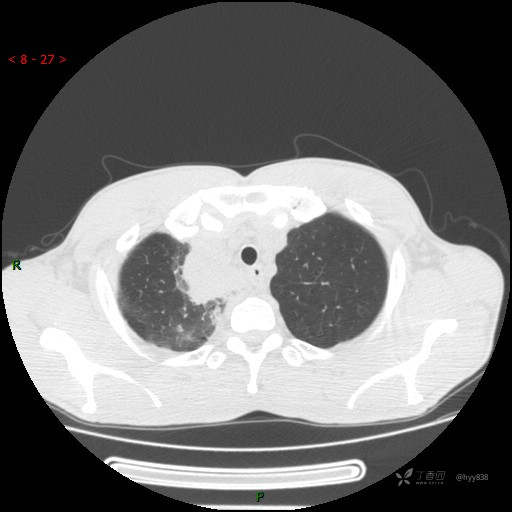

胸部CT平扫